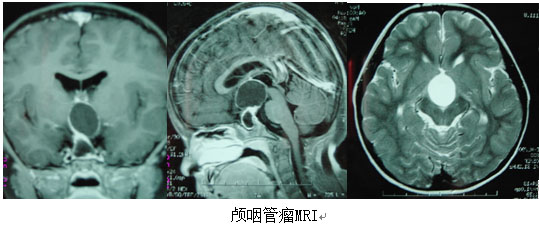

颅咽管瘤是指发生于颅咽管残余上皮细胞的肿瘤,是常见的先天性肿瘤,约占60%,占颅内肿瘤的5%—6%。为良性肿瘤,可见任何年龄,以儿童及青年多见,男女比例约为2:1。临床表现主要为头痛、呕吐、视力减退、视野缺损及视神经萎缩;发育迟缓,性功能障碍,女性月经不调、闭经、不孕,男性性欲减退、阳萎;体温调节失常、多饮、多尿、消瘦、精神异常;向邻近生长者可有偏瘫、感觉减退等相应压迫症状、体征。手术治疗为首选,年龄越小,越易全切,并发症越少,故早诊早治是关键。

颅咽管瘤起源于垂体胚胎发生过程中残存的扁平上皮细胞,是一种常见的先天性颅内良性肿瘤,大多位于蝶鞍之上,少数在鞍内。颅咽管...【详细】